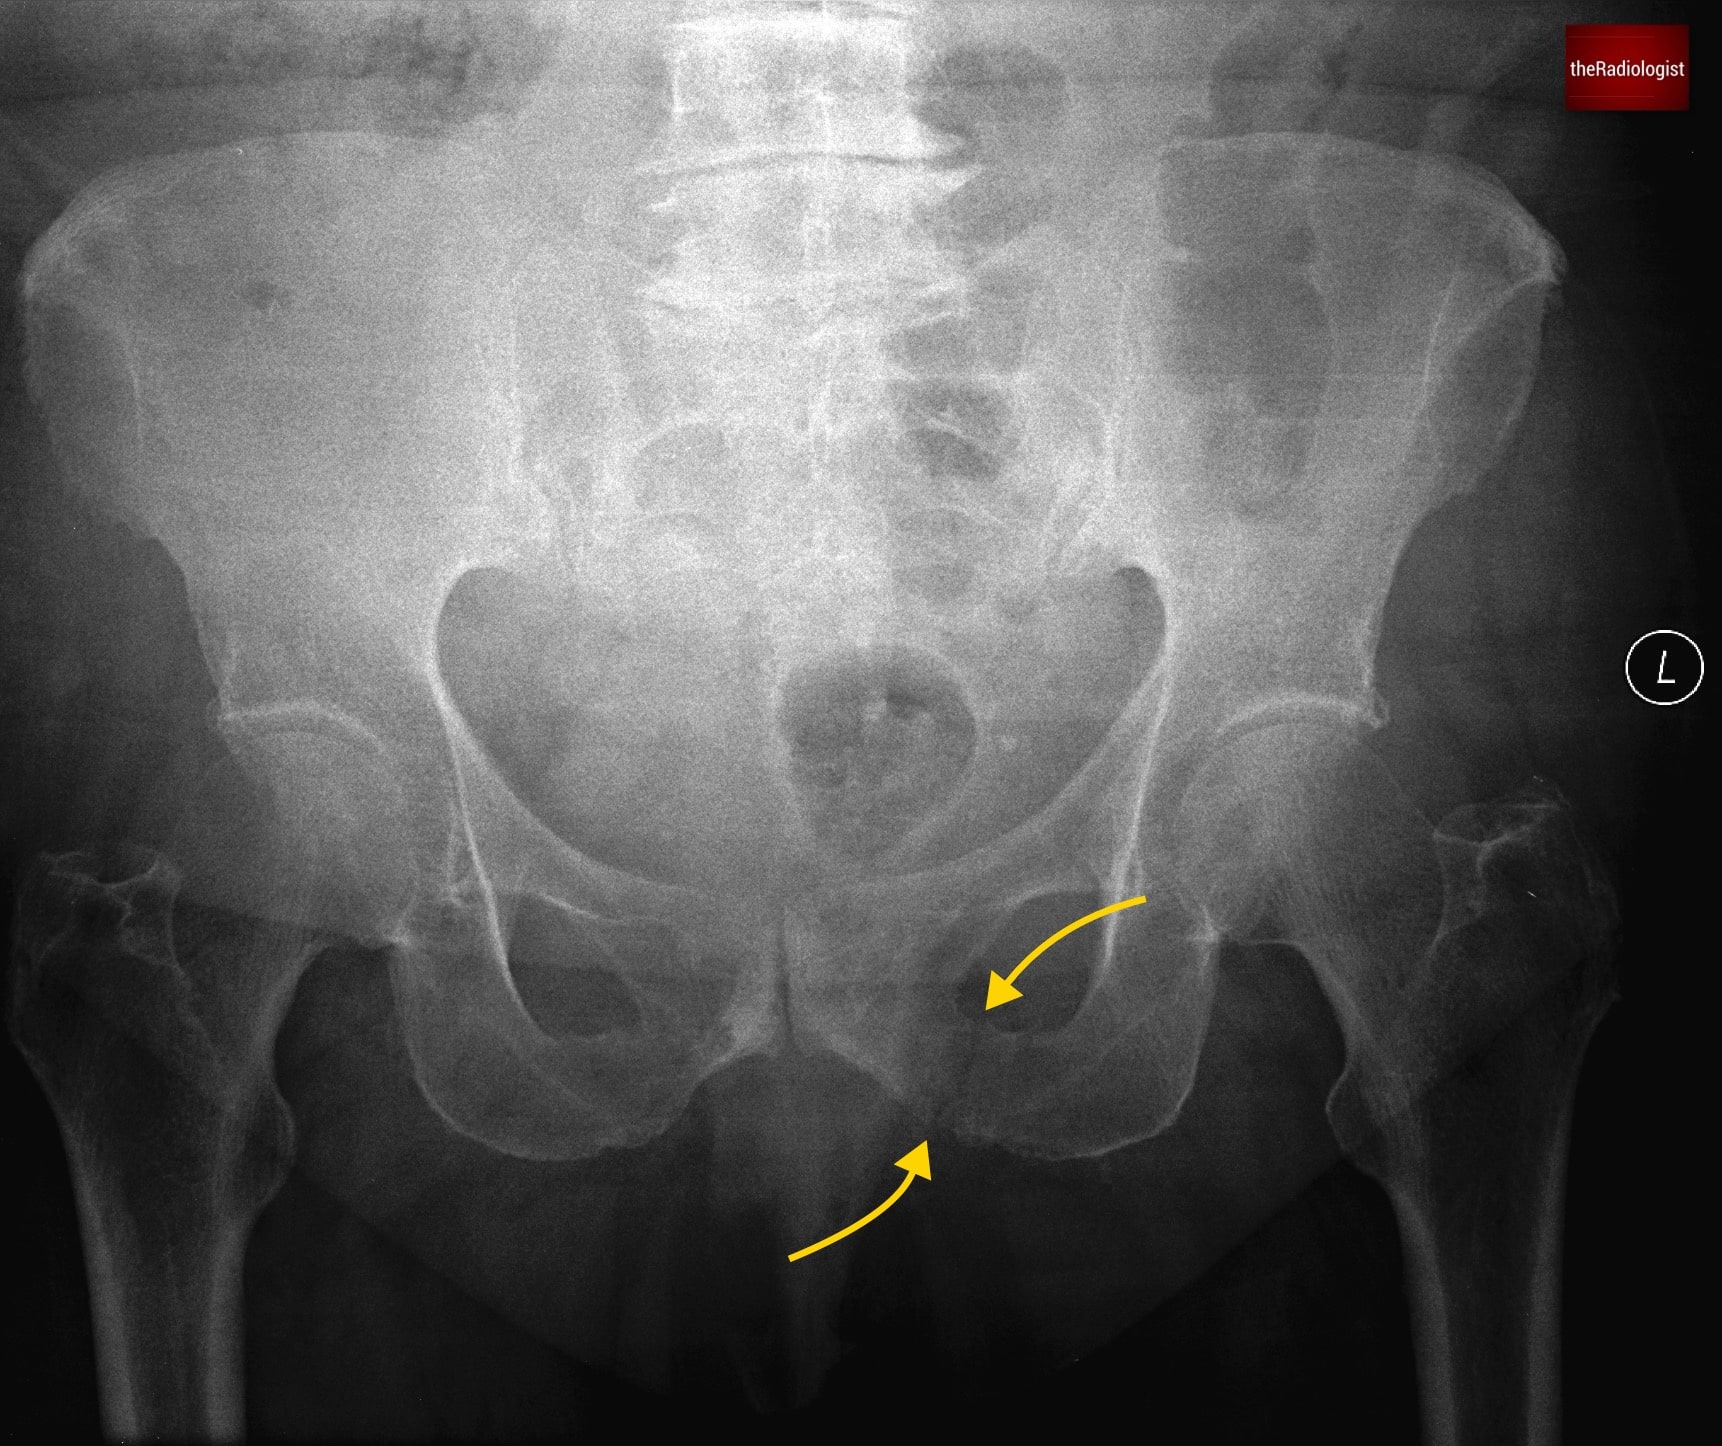

P: Pubic rami

Trace both superior and inferior pubic rami carefully. These are common fracture sites, especially in low-energy trauma in older patients. Fractures may appear only as faint cortical breaks or irregularities, so look carefully. Always compare both sides for symmetry, and remember: a break in one part of the ring usually means there is a second injury elsewhere.

Pay close attention to both the superior and inferior pubic rami looking for any subtle fractures.

On this film if you follow the cortex of the left sided inferior pubic ramus you will see a break in the cortex and a fracture line.